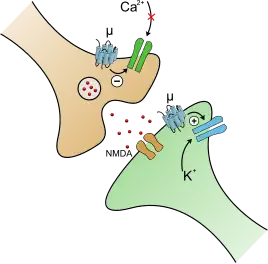

There are three principal classes of opioid receptors: μ, κ, δ (mu, kappa, and delta),[133] although up to seventeen have been reported, and include the ε, ι, λ, and ζ (epsilon, iota, lambda, and zeta) receptors. Conversely, σ (sigma) receptors are no longer considered to be opioid receptors because their activation is not reversed by the opioid inverse-agonist naloxone. The nociception opioid peptide receptor (NOP) (ORL1) is an opioid receptor that is involved in pain responses, anxiety, movement, reward, hunger, memory, and much more. It plays a major role in the development of tolerance to μ-opioid receptor agonists.[134]

The μ-opioid receptor is responsible for the analgesic, euphoric, and adverse effects of opioids. The μ-opioid receptor is a G protein-coupled receptor. When the μ-opioid receptor is activated, it causes pain relief, euphoria, constipation, constricted pupils, itching, and nausea.[136] The μ-opioid is located in the gastrointestinal tract, which controls peristalsis. This causes constipation, which can be extremely problematic and distressing. Activation of this receptor also causes relaxation of voluntary and involuntary muscles, which can cause side effects like trouble urinating and swallowing. The μ-opioid receptor can also reduce androgens, thus decreasing libido and sexual function. The receptor is also known to cause "musical anhedonia".[137]

Opioids activate μ-opioid receptors in the rostromedial tegmental nucleus (RMTg). The rostromedial tegmental nucleus is a GABAergic nucleus that functions as a "master brake" for the midbrain dopamine system.[152][153] The RMTg possesses robust functional and structural links to the dopamine pathways.[152][153] Opioids decrease the release of GABA, thus disinhibiting the GABAergic brake on dopamine networks.[152] GABA is an inhibitory neurotransmitter, meaning it either blocks or decreases the potential of neuron firing.[154] This causes large amounts of dopamine to be released, as it is no longer blocked by GABA.[152] Disinhibition of GABA may be responsible for causing seizures, an uncommon adverse effect of opioids. GABAergic disinhibition is also why opioids are not considered true depressants. This excitement of dopaminergic pathways causes the euphoria of opioids. This causes major positive reinforcing effects in the brain, instructing it to do it again. The RMTg is also responsible for the development of tolerance and addiction. Psychostimulants also excite this pathway.[152][153]